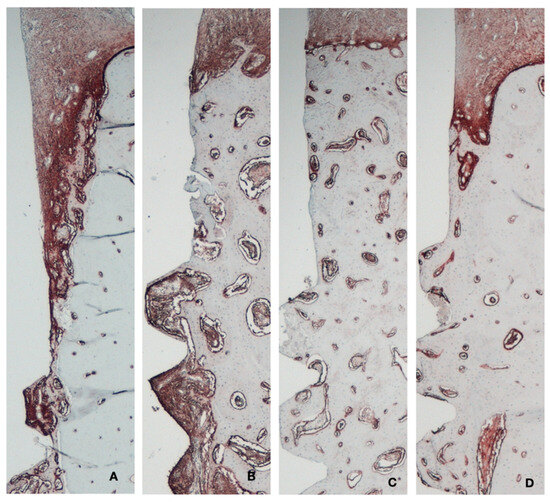

3.2. Histology and Histomorphometry

3.3. Histometric Results

3.4. Immunohistochemical Results

3.5. Bone Metabolism